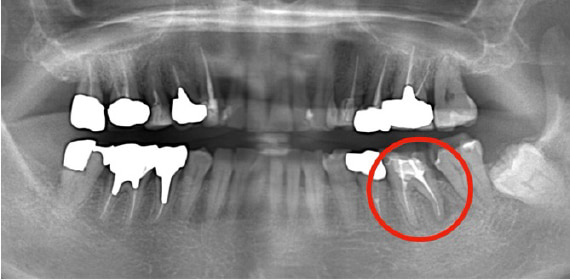

近所のかかりつけの歯科医院で、「再治療できないから奥歯を抜くしかない」と言われた。

あきらめきれず、HPで探して当院へ来院。

外すと中がドロドロに虫歯に感染していました。

折れて残っていた機具を除去

根管の中を洗浄し、無菌に近い空の状態にした。

根管の中を封鎖し終了。

治療後病気がなくなり骨が再生した